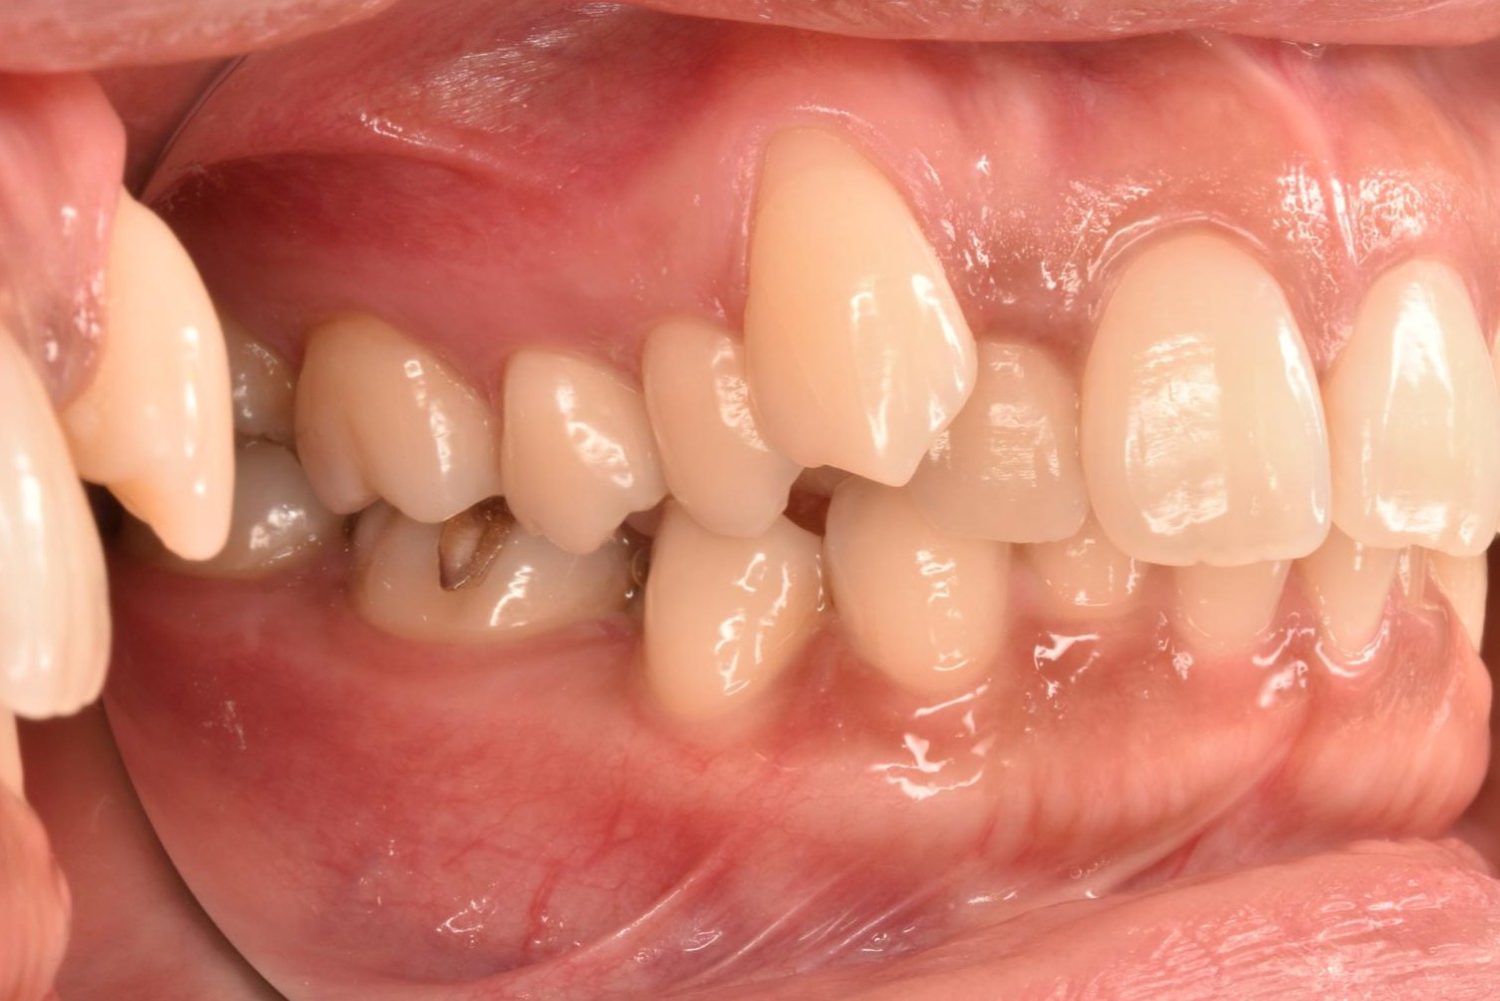

| 主訴 | 20代女性の患者さん。右上の八重歯が突出しており、前歯の見た目にコンプレックスを抱いていた。下顎の左右第2小臼歯(5番)が舌側に大きく傾斜しており、食事の際に、食べかすが詰まりやすく日常的に不快感を覚えていた。噛み合わせの改善と、見た目のバランスを整えたいという希望があり、矯正治療を行うことになった。また、目立ちにくい方法で治療を進めたいという意向から、マウスピース型装置の矯正 “インビザライン”を希望。 |

| 治療内容 | 下顎の左右第2小臼歯(5番)は舌側に大きく傾斜しており、矯正治療における歯の移動効率や全体の歯列バランスを考慮し、便宜抜歯を行った。また、上顎の左右第1小臼歯(4番)についてもスペース確保の目的で抜歯を実施し、全顎的な歯列の配列を円滑に進められるよう計画。矯正装置は、患者さんのなるべく目立ちにくい治療を行いたいという強い希望とライフスタイルに合わせて、マウスピース型矯正装置「インビザライン」(※1)を採用。抜歯が必要となる矯正治療は、診断・治療の難易度が高い方法である。当院ではCTやセファログラムなどの先進的な設備を完備し、多角的な診査診断と豊富な臨床経験をもつ理事長による治療を行うことで、このような難症例にも対応可能。 また、当院は矯正治療だけでなく、むし歯治療やクリーニングなどの一般歯科・予防治療も一貫して管理する包括的な審美治療を行う総合クリニック。治療中にむし歯などの問題が見つかっても、すぐに対応できるため、患者さんの通院の負担をできる限り抑えたスムーズな対応が可能。矯正専門医院ではできない包括的なサポート体制こそが、シャングリラデンタル横浜歯科矯正歯科で矯正治療を受けるメリットである。 矯正治療中は定期検診で経過の確認とクリーニングを行い、必要に応じて治療計画の見直しやマウスピース型装置の追加を行った。患者さんの高い装着遵守率も相まって、歯列は順調に整い、機能的にも審美的にも良好な結果をえることができた。 (※1)未承認医薬品等であるため医薬品副作用被害救済制度の対象とはならない可能性があります。 |